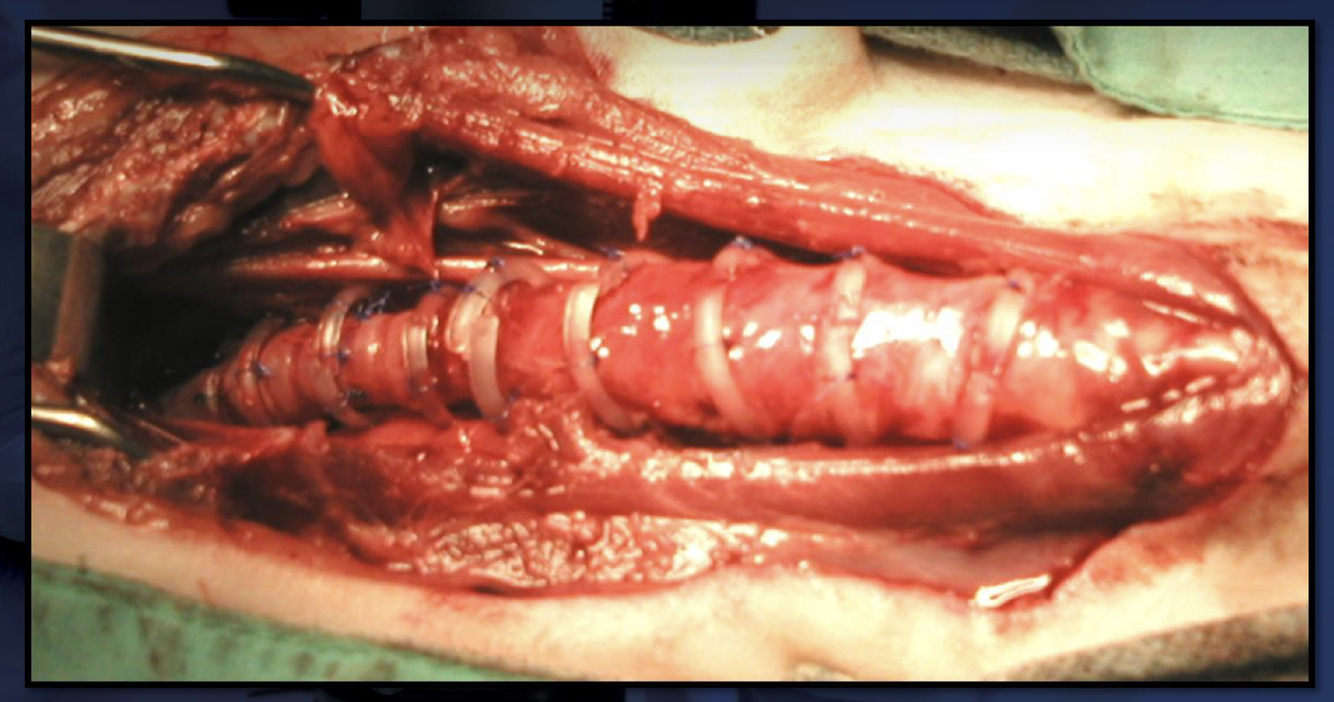

What are the 2 types of extraluminal repair of collapsed tracheas?

1. Hobson rings - syringe containers are cut into rings and have holes drilled in them for the placement of tack sutures

2. new generation devices - pre-made rings with notches to tie sutures

placed every centimeter from larynx to the heart base